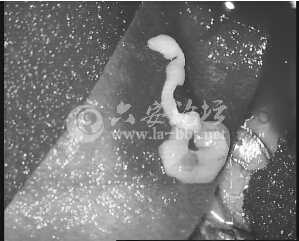

开颅手术时,医生用镊子小心翼翼地将张敏(化名)大脑里的白色异物夹出,放在手术台上两秒钟后,白色物体竟然动起来了,医生很惊讶“原来是条虫”。至此,困扰张敏半年之久的癫痫之谜,才算最终解开。医生怀疑,这与小张吃了不干净的食物有关系。通讯员徐晓蓉现代快报记者刘峻

大脑里夹出3厘米长的虫子

8月14日,张敏上了手术台进行开颅手术。术中,杨坤将白色像棉线一样的异物夹出来后,最初还没有意识到是什么东西。“放在手术台上的时候,它竟然动起来了,我当时就想到,这是寄生虫。”杨坤说,“我们量了一下,虫子有3厘米长。”